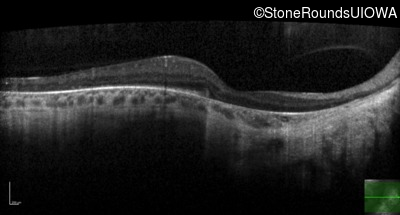

This 46 year old man first had difficulty driving at night in his mid-thirties. Clinically focused genetic testing for Choroideremia was negative.

| XL Choroideremia | CHM | Insertion of 212.3kb of Chr. 3 in intron 2 (IVS2+15,016 ins 212.3kb) | XL |